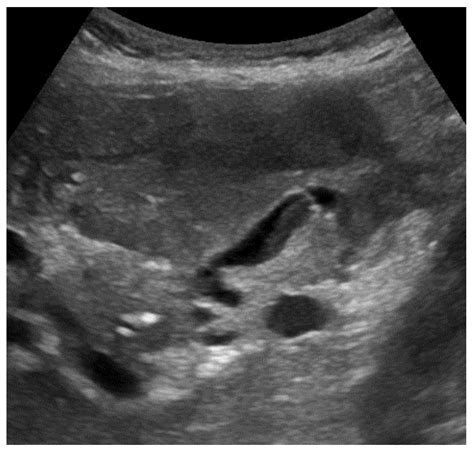

The primary advantage of using an ultrasound for gallbladder problems is its unmatched ability to identify gallstones. Because gallstones are often calcified or dense, they reflect sound waves differently than the surrounding fluid-filled gallbladder, making them clearly visible on the monitor. Furthermore, ultrasound is highly efficient at detecting signs of inflammation, such as a thickened gallbladder wall or the presence of fluid around the organ, which are indicators of cholecystitis.

Cholelithiasis (Gallstones) Highly reflective (echogenic) spots within the gallbladder, usually with a characteristic "acoustic shadow" behind them.

Gallbladder Sludge A collection of particulate matter that moves slowly; it does not usually cast a shadow like stones do.